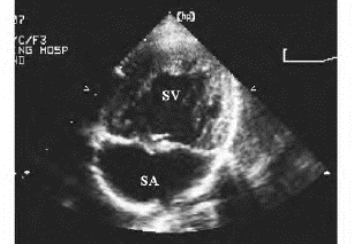

图17-8 单心室二维超声图

心尖四腔切面,显示心房及心室之间未间隔回声,呈单心房、单心室结构